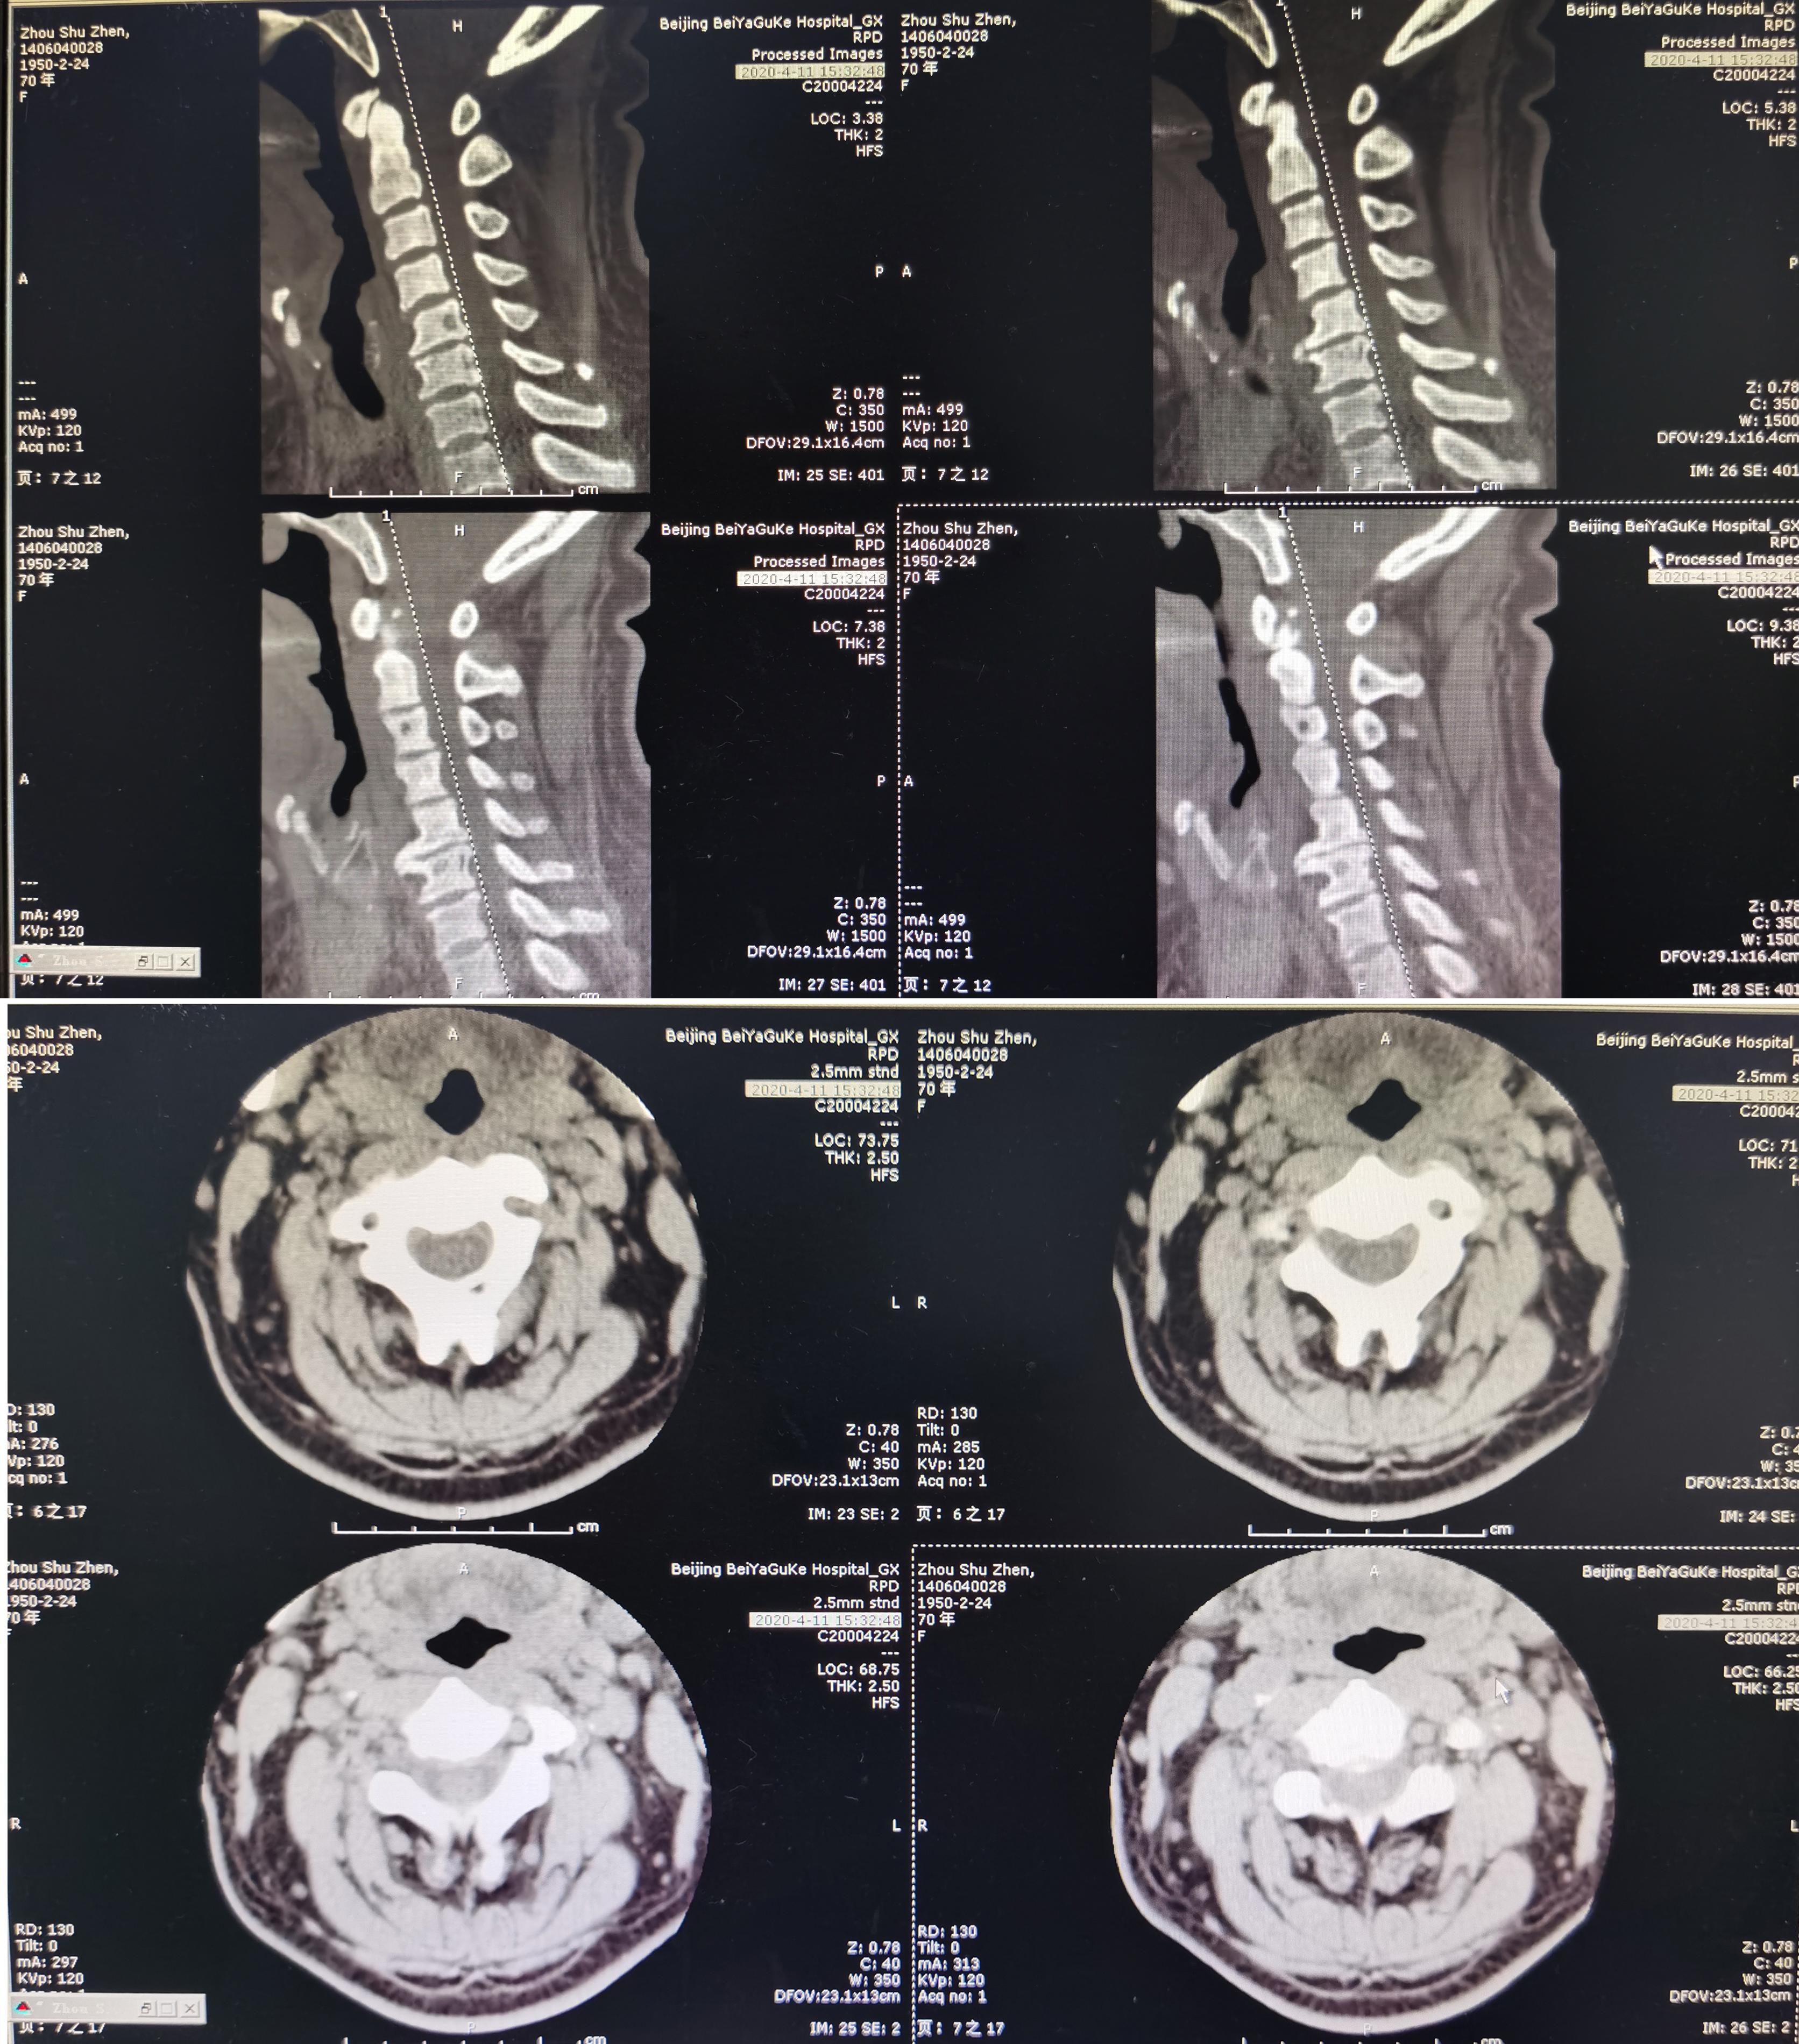

患者因间断性头晕、行走不稳,伴双上肢放射痛,麻木,于2020年4月11日入住北京某三级医院的中医骨伤科,当日查颈椎CT示椎管狭窄性颈椎病(图-1)。

图-1: 2020年4月11日颈椎CT